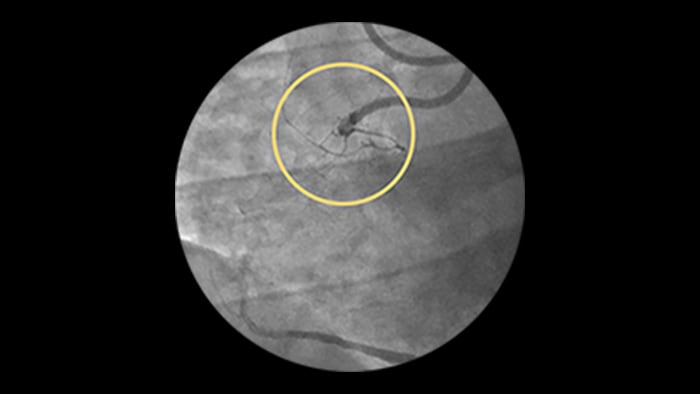

– Stent length is an independent predictor of in-stent restenosis and thrombosis.

– Stenting long segments with multiple and or overlapping stents may lead to injury to the vessel wall integrity.